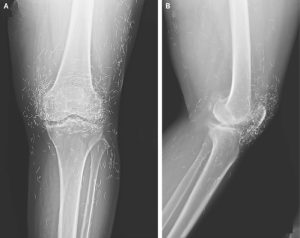

Embedded needles may lead to inflammation, infection, or abscesses, and the body may react by forming fibrous tissue around them. Doctors also note that such objects can complicate medical imaging. The presence of metal may obscure X-ray results and can make MRI scans dangerous, as metal fragments could move and damage nearby tissue or blood vessels.